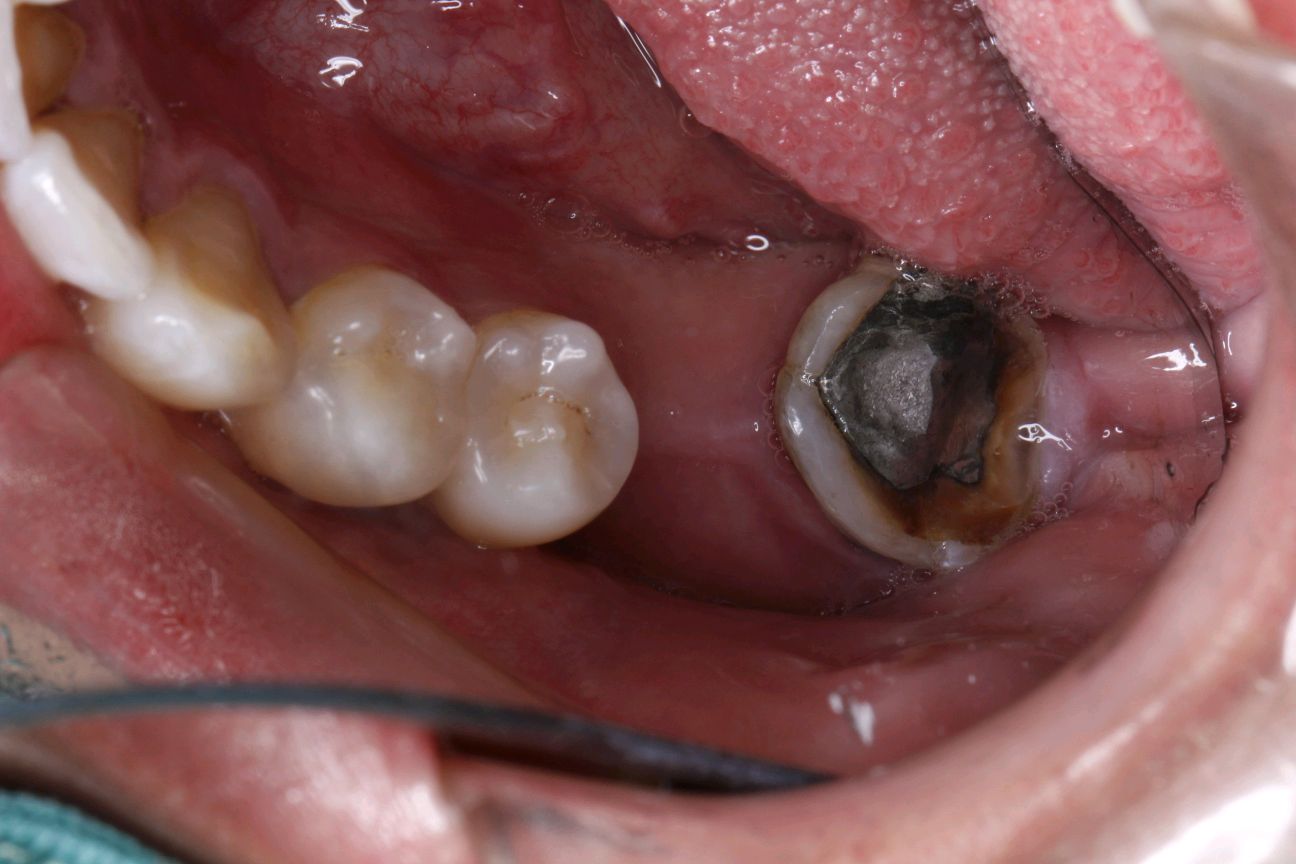

患者做完根管治疗后没有及时进行冠修复,吃东西的时候把原来做过根管治疗的牙齿咬裂了。检查可见:近中邻颌面牙劈裂,至龈下3~4mm,颌面大面积银汞充填物。牙体松动+,探(-),扣(+)。X线示根尖周呈低密度影像。向患者解释病情及治疗方案,患者选择拔除后以种植牙填补空缺。